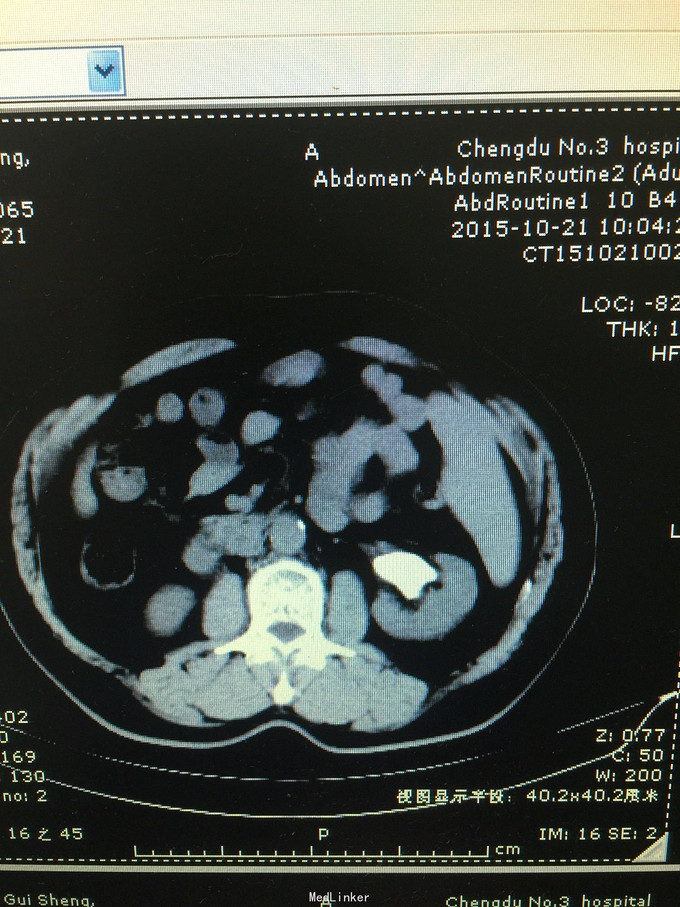

患者男,59岁,因检查发现左肾巨大铸型结石3天入院 病史:患者检查发现左肾结石,无发热,无血尿,无腰痛,食欲,睡眠均正常。

诊断考虑左肾铸型结石。 处理:经皮肾球囊扩张,钬激光加气压弹导碎石,手术顺利,术中术后出血少,术后复查未见结石残留。患者痊愈出院。